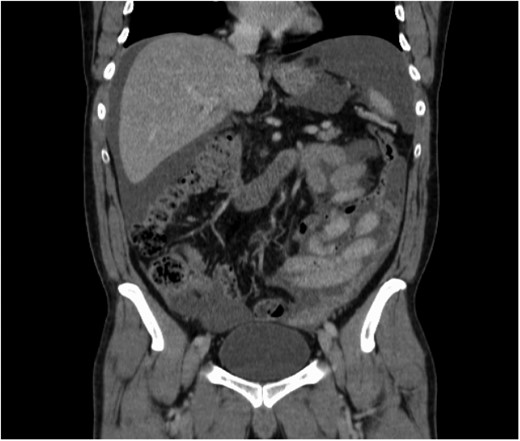

After discussion in radiology MDT, an ultrasound-guided omental implant biopsy was taken. Post-procedure, he developed abdominal pain, fever and increasing CRP. Histology showed cores comprising bowel walls, chronic inflammatory infiltrates and numerous plasma cells and mesothelial cells in serosa, but no malignancy was seen. Repeat CT-AP reported a slight increase in the volume of ascites with mild peritoneal enhancement in the pelvis suggesting early/mild peritonitis; however, no free air was identified (Fig. 2).

Increase in the amount of ascites post-ultrasound-guided biopsy.